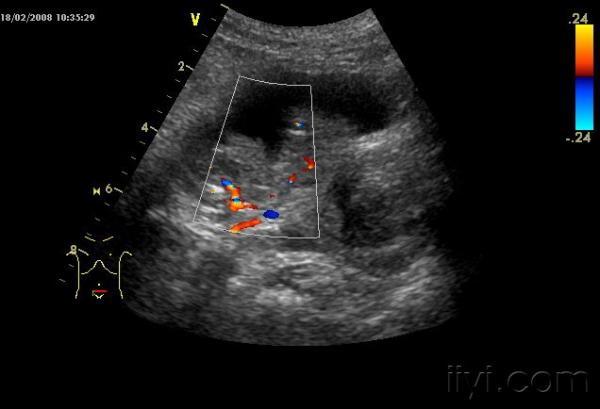

肿瘤内丰富血流

频谱呈高速血流